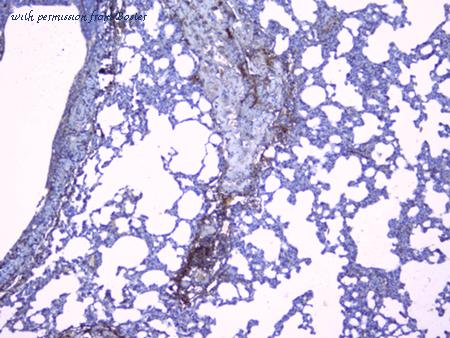

gene information - mouse Col3a1

- synonym:AW550625; Col3a-1; Tsk-2; Tsk2; collagen alpha-1(III) chain; procollagen, type III, alpha 1

- description:collagen, type III, alpha 1